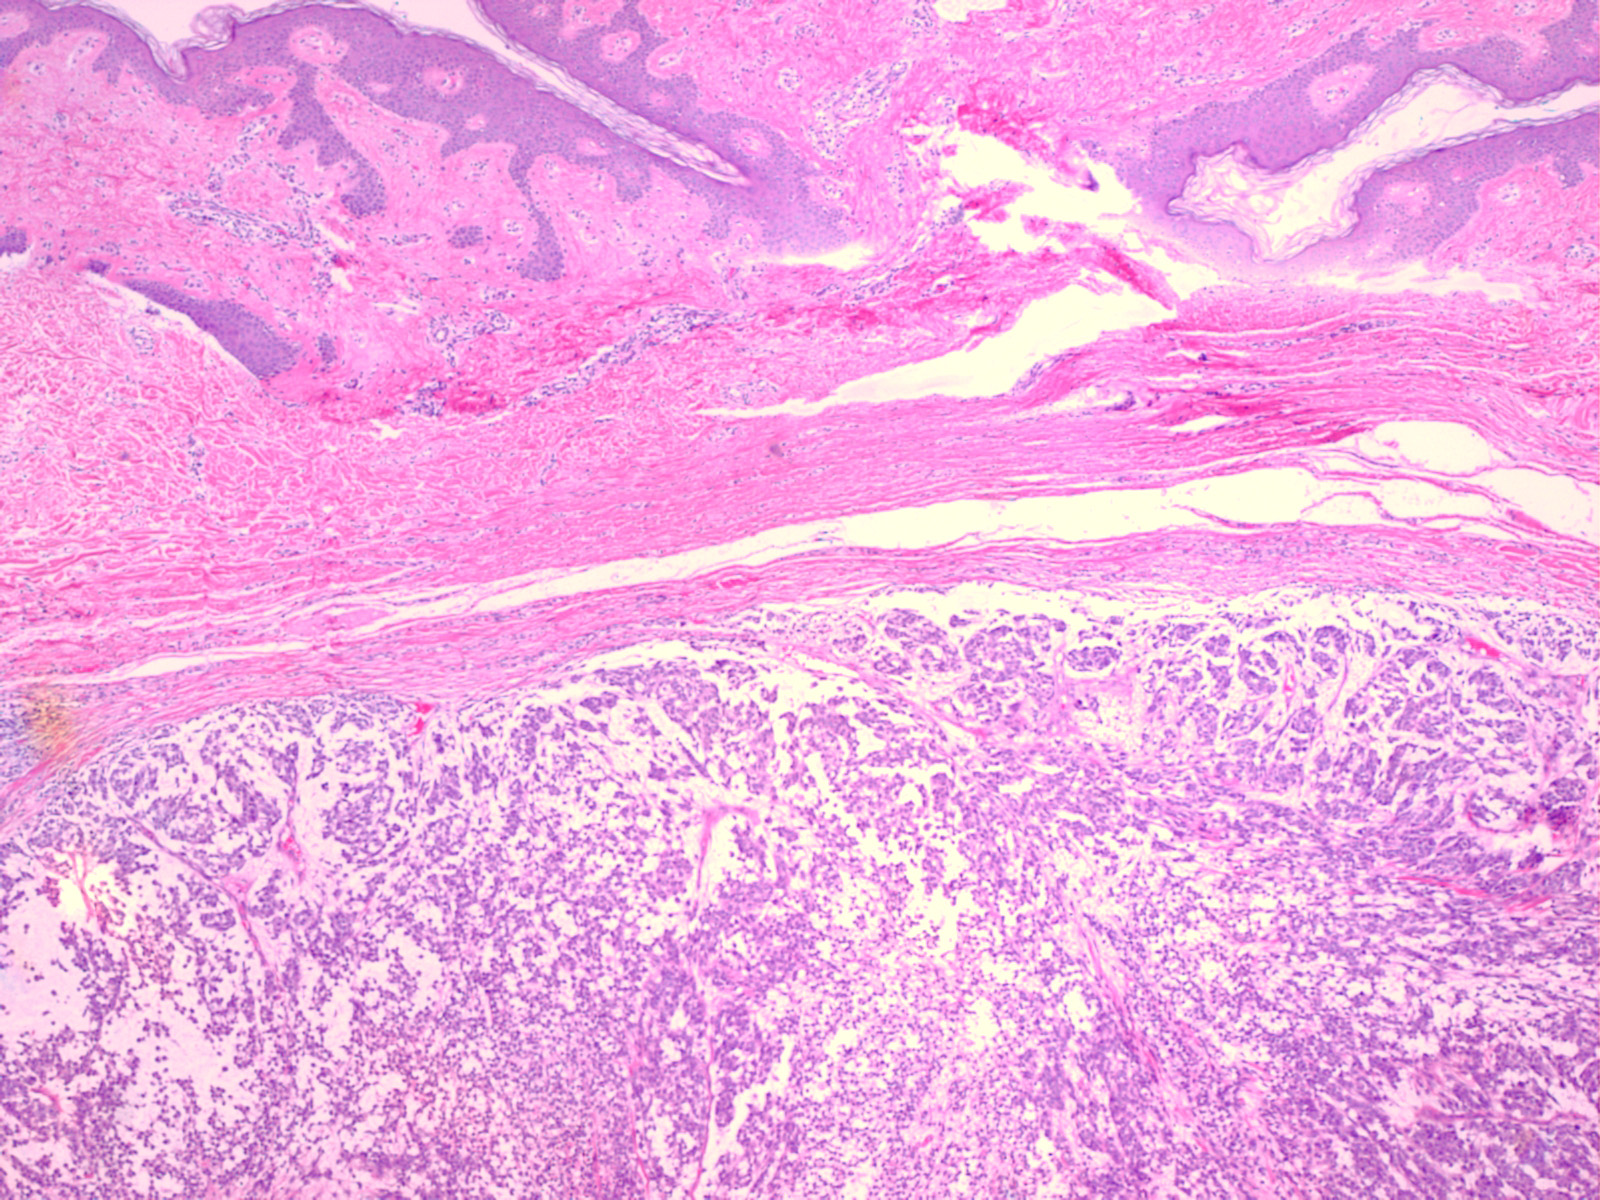

melanoma_mucinous